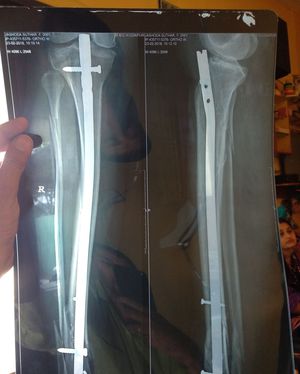

Guess they forgot to measure the nail😕

Wrong

Febula is not repaired

They don’t usually repair the fibula especially in proximal fractures or diaphysis fractures. They will sometimes repair the lateral malleolus

Also rod size is larger

who did this? its totally off...

This looks like a very botched surgery. Her recovery time is going to be very very long. 😭😭